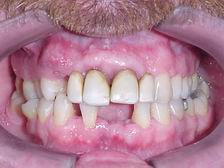

ANTES

DEPOIS